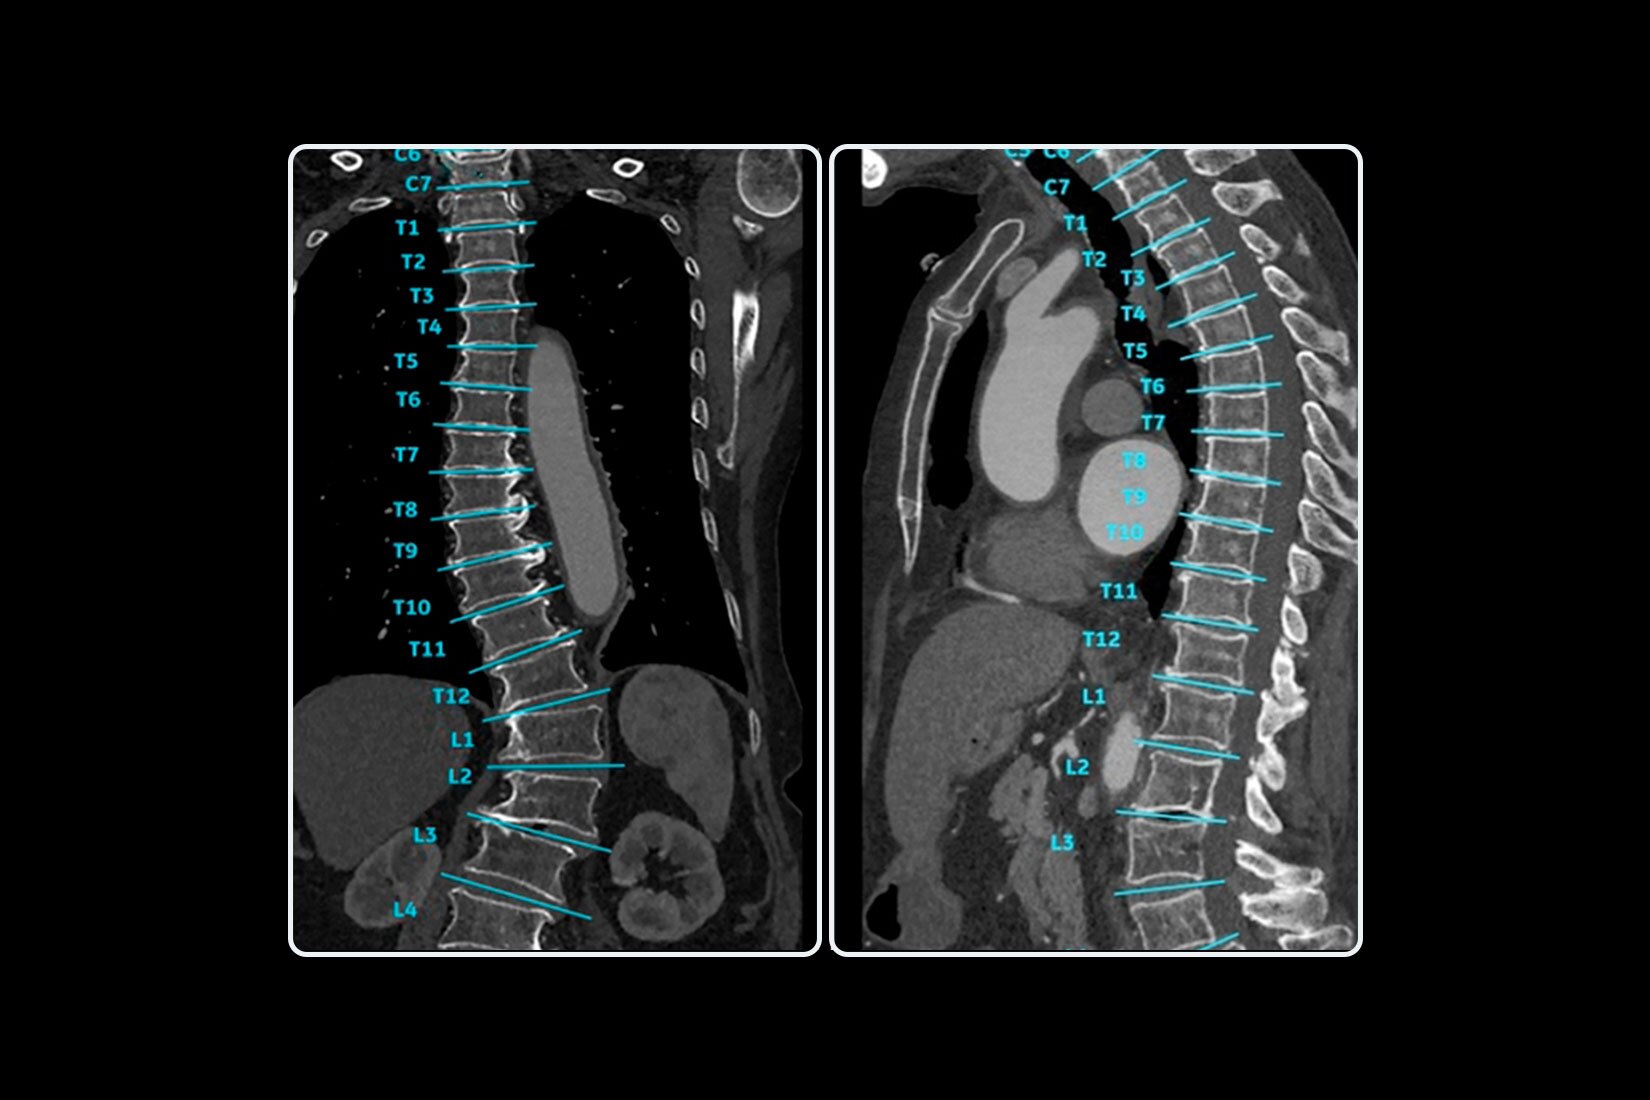

TrueFidelity™ DL is our state-of-the-art image reconstruction technology that uses a DNN to generate high-definition, low-noise CT images. It produces images with exceptional sharpness, low-contrast image quality performance and your preferred noise texture, at the same dose.¹

Available on all Revolution Ascend Platform configurations, Effortless Workflow intelligently automates your CT workflow from pre-scan protocoling to post-scan processing. It uses AI-based features to help transform the entire CT experience and provides maximum efficiency, accuracy, clarity and consistency.

This enables technologists to automatically and accurately personalize scans for each patient with significantly less effort. The end result is a beautiful CT image acquired in less time.